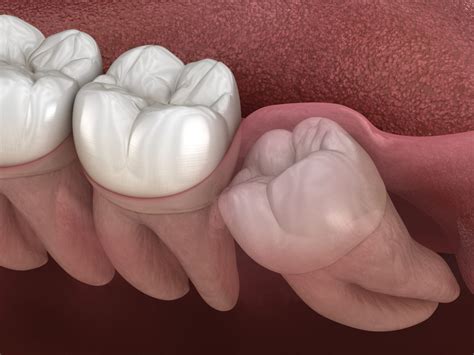

Discovering that you have a partially erupted wisdom tooth can be a source of significant discomfort and concern. Often referred to as "impacted" or "partially impacted," these third molars struggle to fully emerge through the gum tissue due to a lack of space in the jaw or an unfavorable angle of growth. Because the tooth is only partially visible, it creates a unique set of oral hygiene challenges that can quickly lead to infection, pain, and damage to surrounding teeth. Understanding why this happens, how to identify the symptoms, and what steps to take is crucial for maintaining your long-term oral health.

A partially erupted wisdom tooth occurs when the tooth breaks through the gum line but fails to emerge completely into its proper functional position. Instead of sitting flush with your other teeth, a portion of the crown remains covered by a flap of gum tissue, medically known as an operculum. This small flap creates a pocket between the tooth and the gum, which is notoriously difficult to clean.

Damage to Adjacent Teeth The pressure from an angled wisdom tooth can damage the roots of healthy, functional second molars.